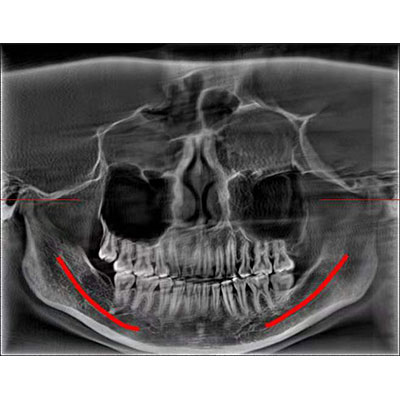

通過(guò)三維容積影像,提取高清口腔全景影像。